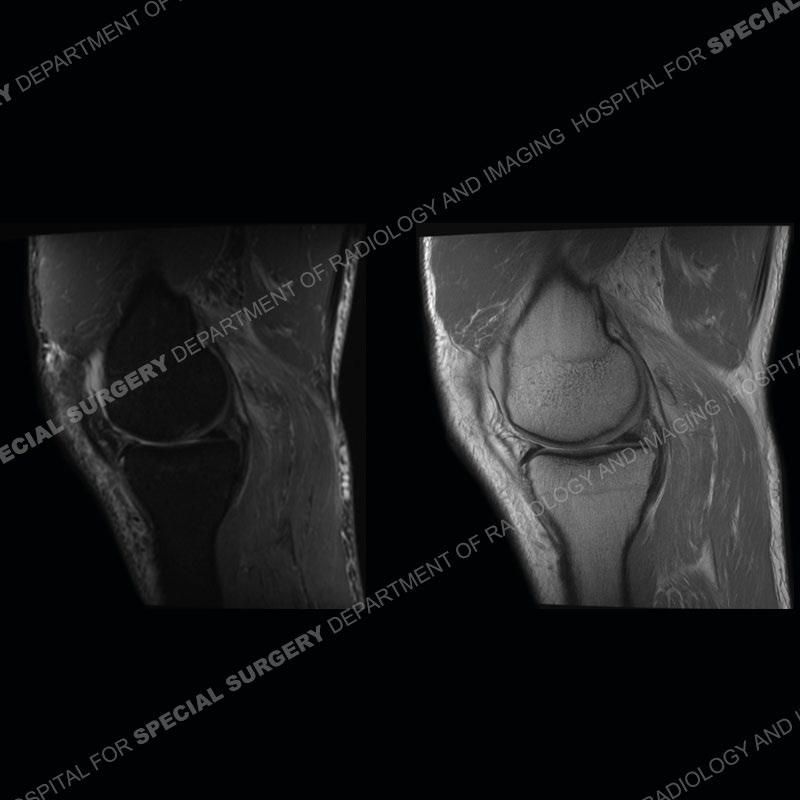

The radiographs show degenerative change of the medial compartment and a varus knee, but they are not germane to this case. No acute bony injury is present. The MRI shows edema of the posterior medial knee/soft tissue and a focal area of a partially disrupted low signal structure. The details are kept at a minimum in the findings of this case on purpose.

Fourth, use all imaging planes and different pulse sequences to make your diagnosis. The edema highlighted in this case can be seen as the obscuration of fat on the PD images but is much easier to perceive as the high signal on the IR pulse sequences. The actual disruption of the MHG myotendinous junction is only able to be seen on the axial images. On the sagittal and coronal images, we get a sense something is wrong but hard to be exact. Lastly, when you look at a study and something just seems off (as I would say the sagittal and coronal images do with that dark band of tissue posteriorly), listen to yourself and go through the study slowly and meticulously. Most of the time you will find you were right, and something indeed is present.